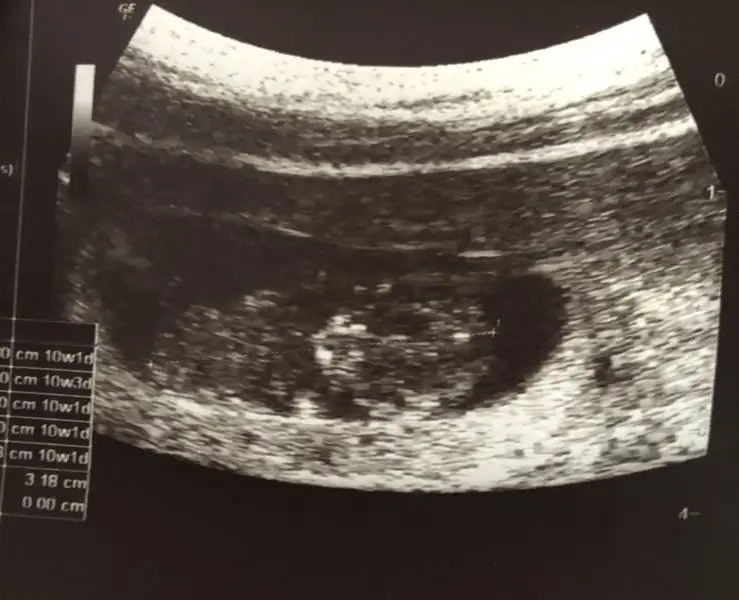

Kızlar merhaba ben bu nün isind3n çok anlamıyorum 10+3 doktor erkeğe benziyor dedi sizce ne yorum yaparmisiniz banada :)